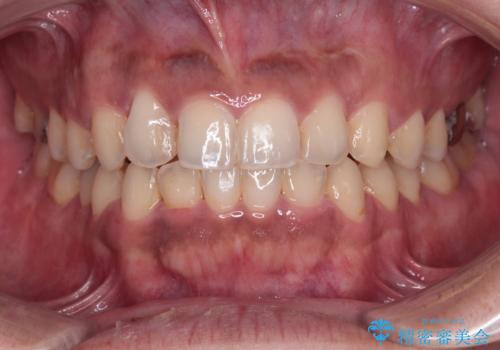

途中2年強の来院がなく、改善されていたデコボコが元に戻ったり、装着時間が不足しており前歯のデコボコは十分に改善することはできませんでしたが、5年間の有効期限内で可能な限り歯列を整えることができました。

前歯が90度近く捻れていたため、しっかりと治すことを考えるとワイヤー矯正の方がおすすめではありましたが、本人の希望によりインビザラインを用いて矯正治療を行うこととしました。

インビザラインは、十分な装着時間が達成されると前歯のデコボコをしっかりと改善できますが、1日の装着時間が20時間に達しなくなると、不十分な仕上がりとなるため、しっかりと装着するよう指示をしました。